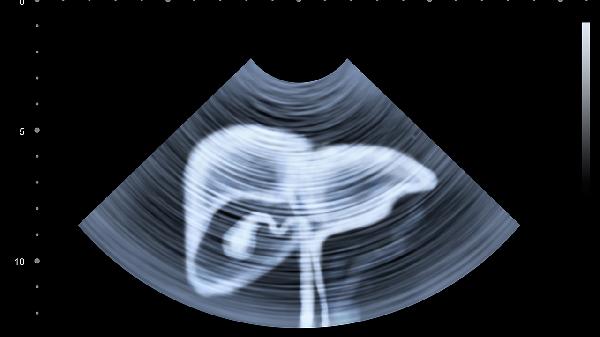

肝脏再生过程分为快速增生期和结构重塑期两个阶段。术后2周内肝细胞会通过加速分裂快速增加体积,此时再生速度可达每日1-2厘米。这个阶段主要恢复肝脏代谢功能,表现为凝血功能指标逐渐正常化。随后进入结构重塑期,肝小叶重新排列构建,胆管血管网络同步再生,此阶段持续3个月以上直至恢复接近原有肝脏形态。临床观察显示,90%以上的活体肝移植供体在术后1年超声检查中,再生肝脏体积可达原肝脏的80%-95%。

术后建议保持优质蛋白饮食,每日摄入鸡蛋、鱼肉等易吸收蛋白有助于肝细胞修复。避免剧烈运动3个月以防止肝脏撕裂,定期复查超声和肝功能。出现持续乏力、黄疸等症状需立即就医。活体肝移植供体的长期随访数据显示,再生肝脏功能与正常肝脏无显著差异,但建议终身避免肝毒性药物使用。